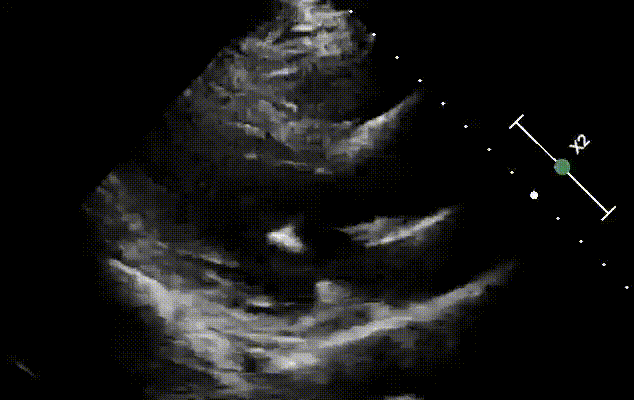

出院前超声

术后患者恢复顺利,原有胸闷气喘、不能平卧等症状消失,术后第二天(40小时)即出院回家。